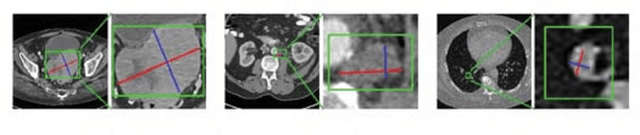

Abstract:Universal lesion detection in computed tomography (CT) images is an important yet challenging task due to the large variations in lesion type, size, shape, and appearance. Considering that data in clinical routine (such as the DeepLesion dataset) are usually annotated with a long and a short diameter according to the standard of Response Evaluation Criteria in Solid Tumors (RECIST) diameters, we propose RECIST-Net, a new approach to lesion detection in which the four extreme points and center point of the RECIST diameters are detected. By detecting a lesion as keypoints, we provide a more conceptually straightforward formulation for detection, and overcome several drawbacks (e.g., requiring extensive effort in designing data-appropriate anchors and losing shape information) of existing bounding-box-based methods while exploring a single-task, one-stage approach compared to other RECIST-based approaches. Experiments show that RECIST-Net achieves a sensitivity of 92.49% at four false positives per image, outperforming other recent methods including those using multi-task learning.